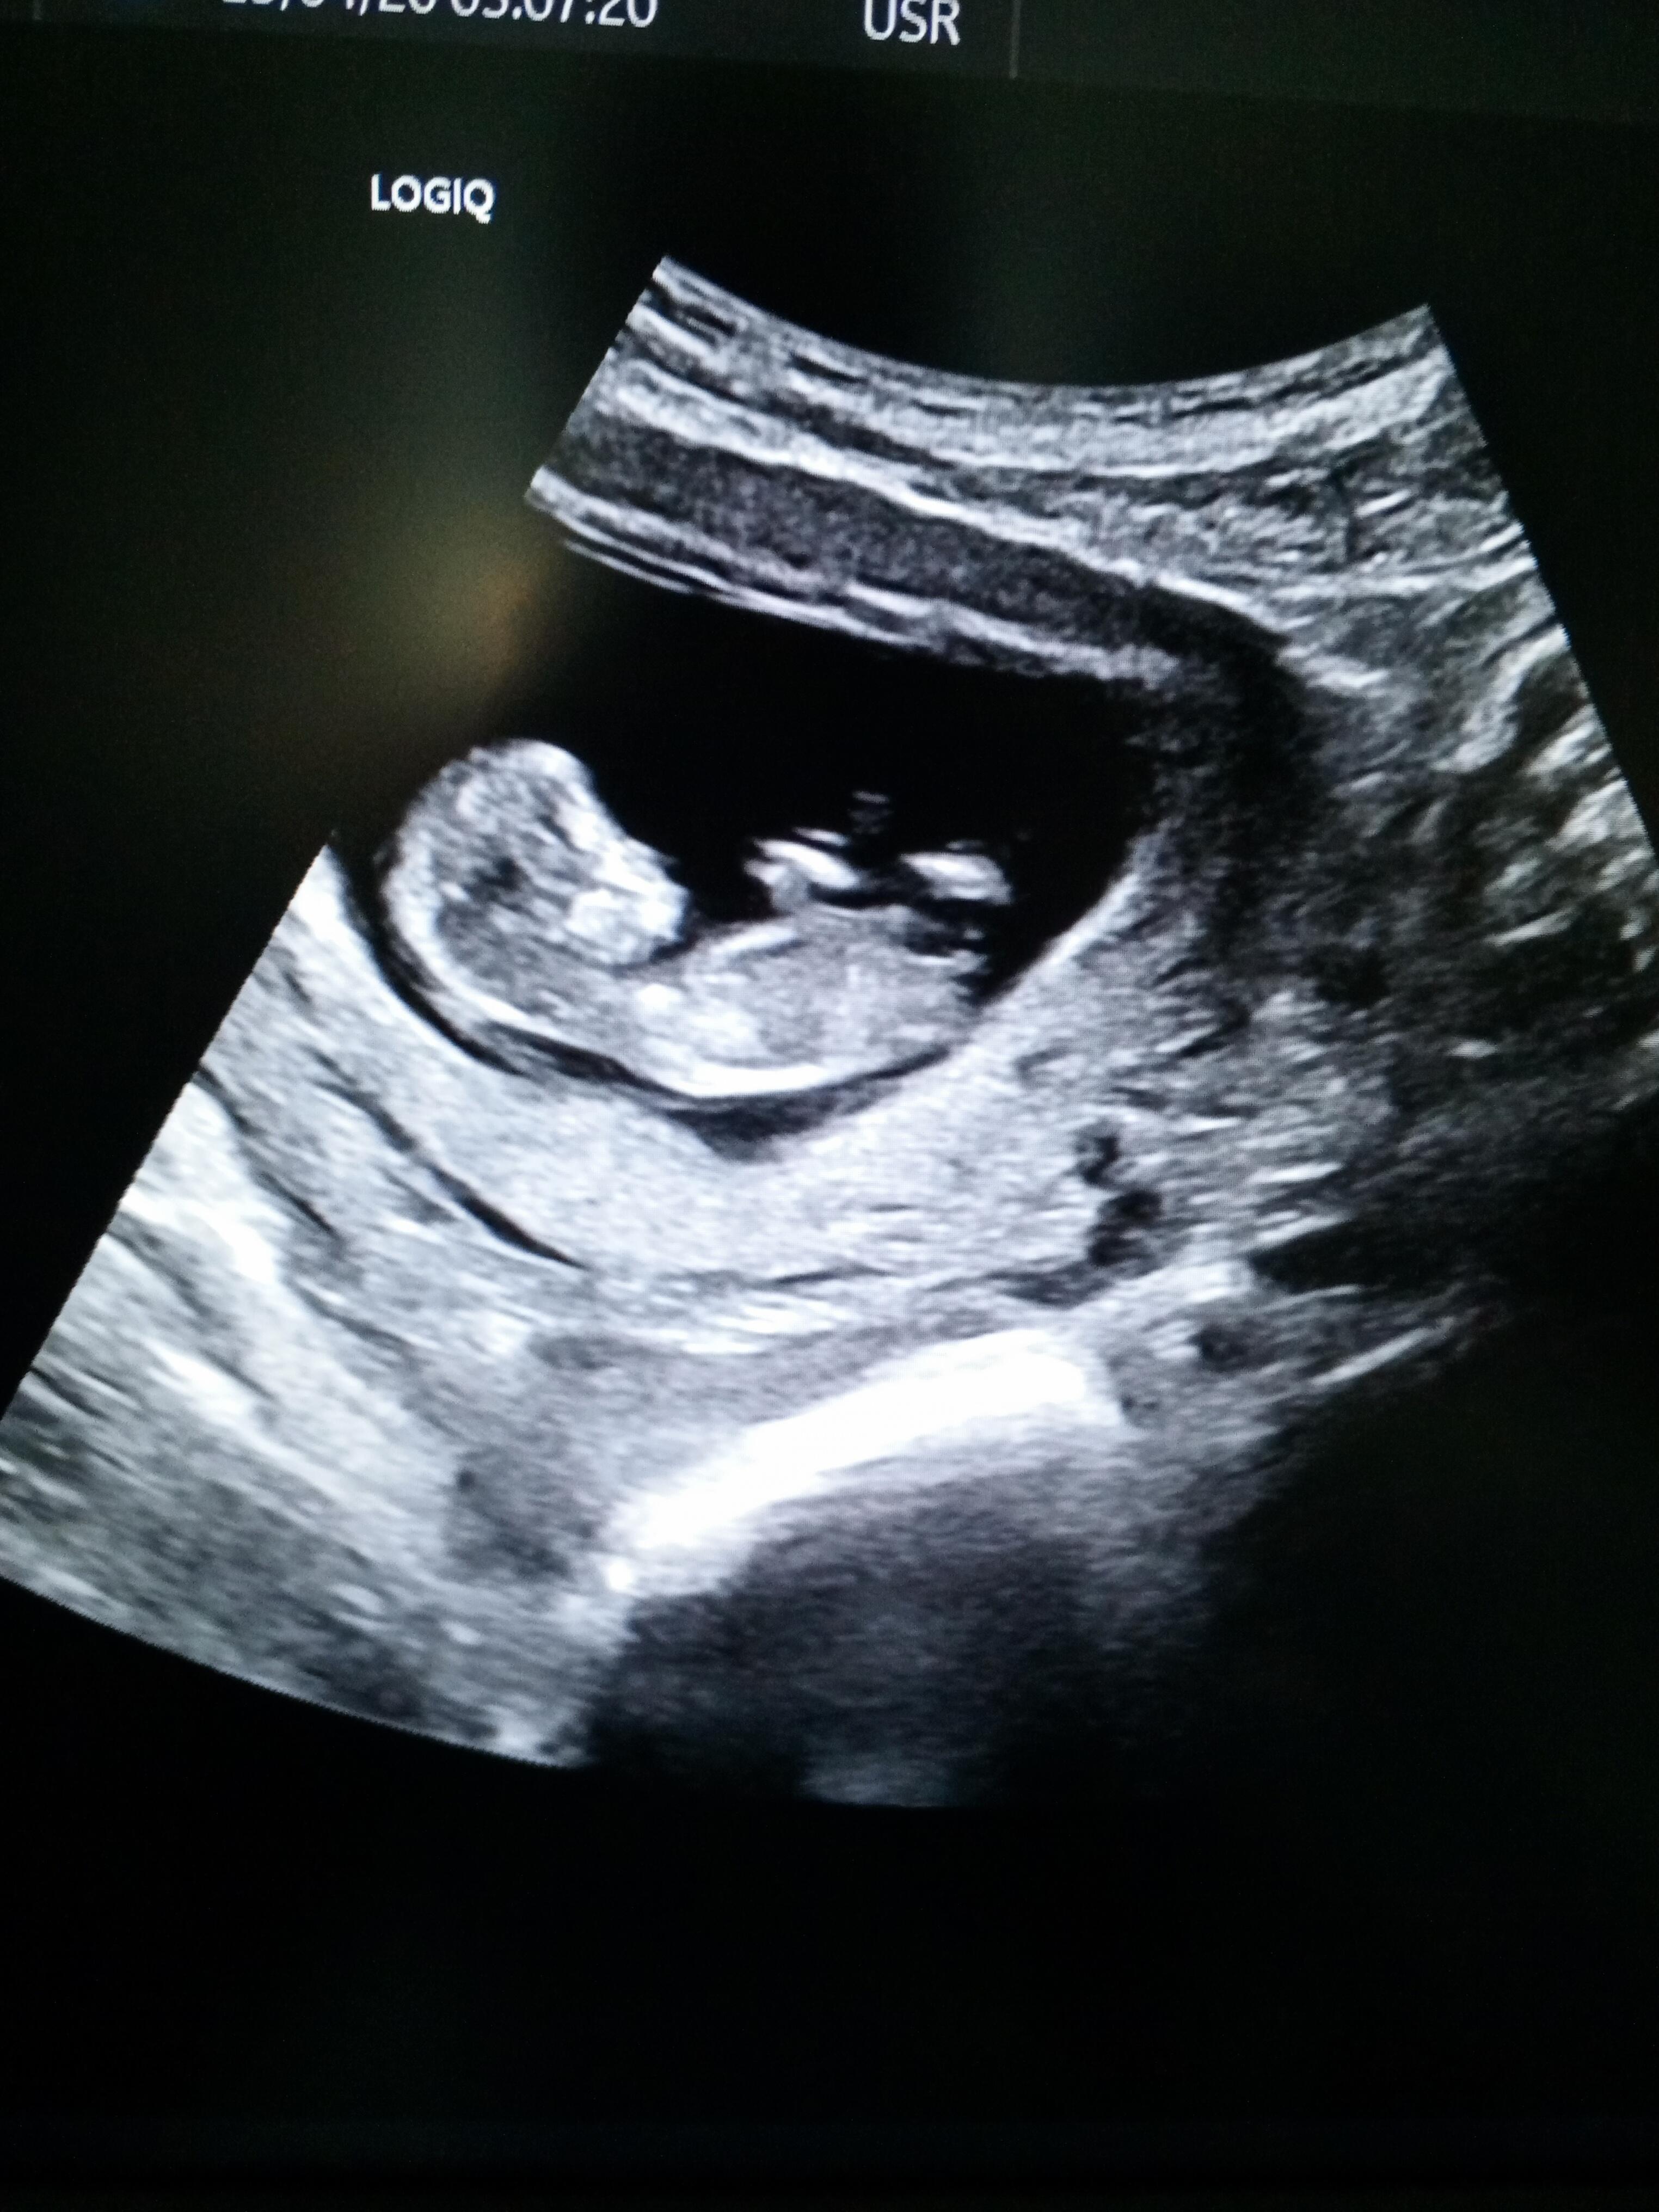

![]()

Kese şekli duruşu erkek bebek gibi ama sonraki attığına bir daha baktım kız gibi başka net var mı canım senin ki sürpriz bebek çözemedim ![]()

Salı günü gitcem kan sonucu göstermeye belki bakarsa atarım ![]()